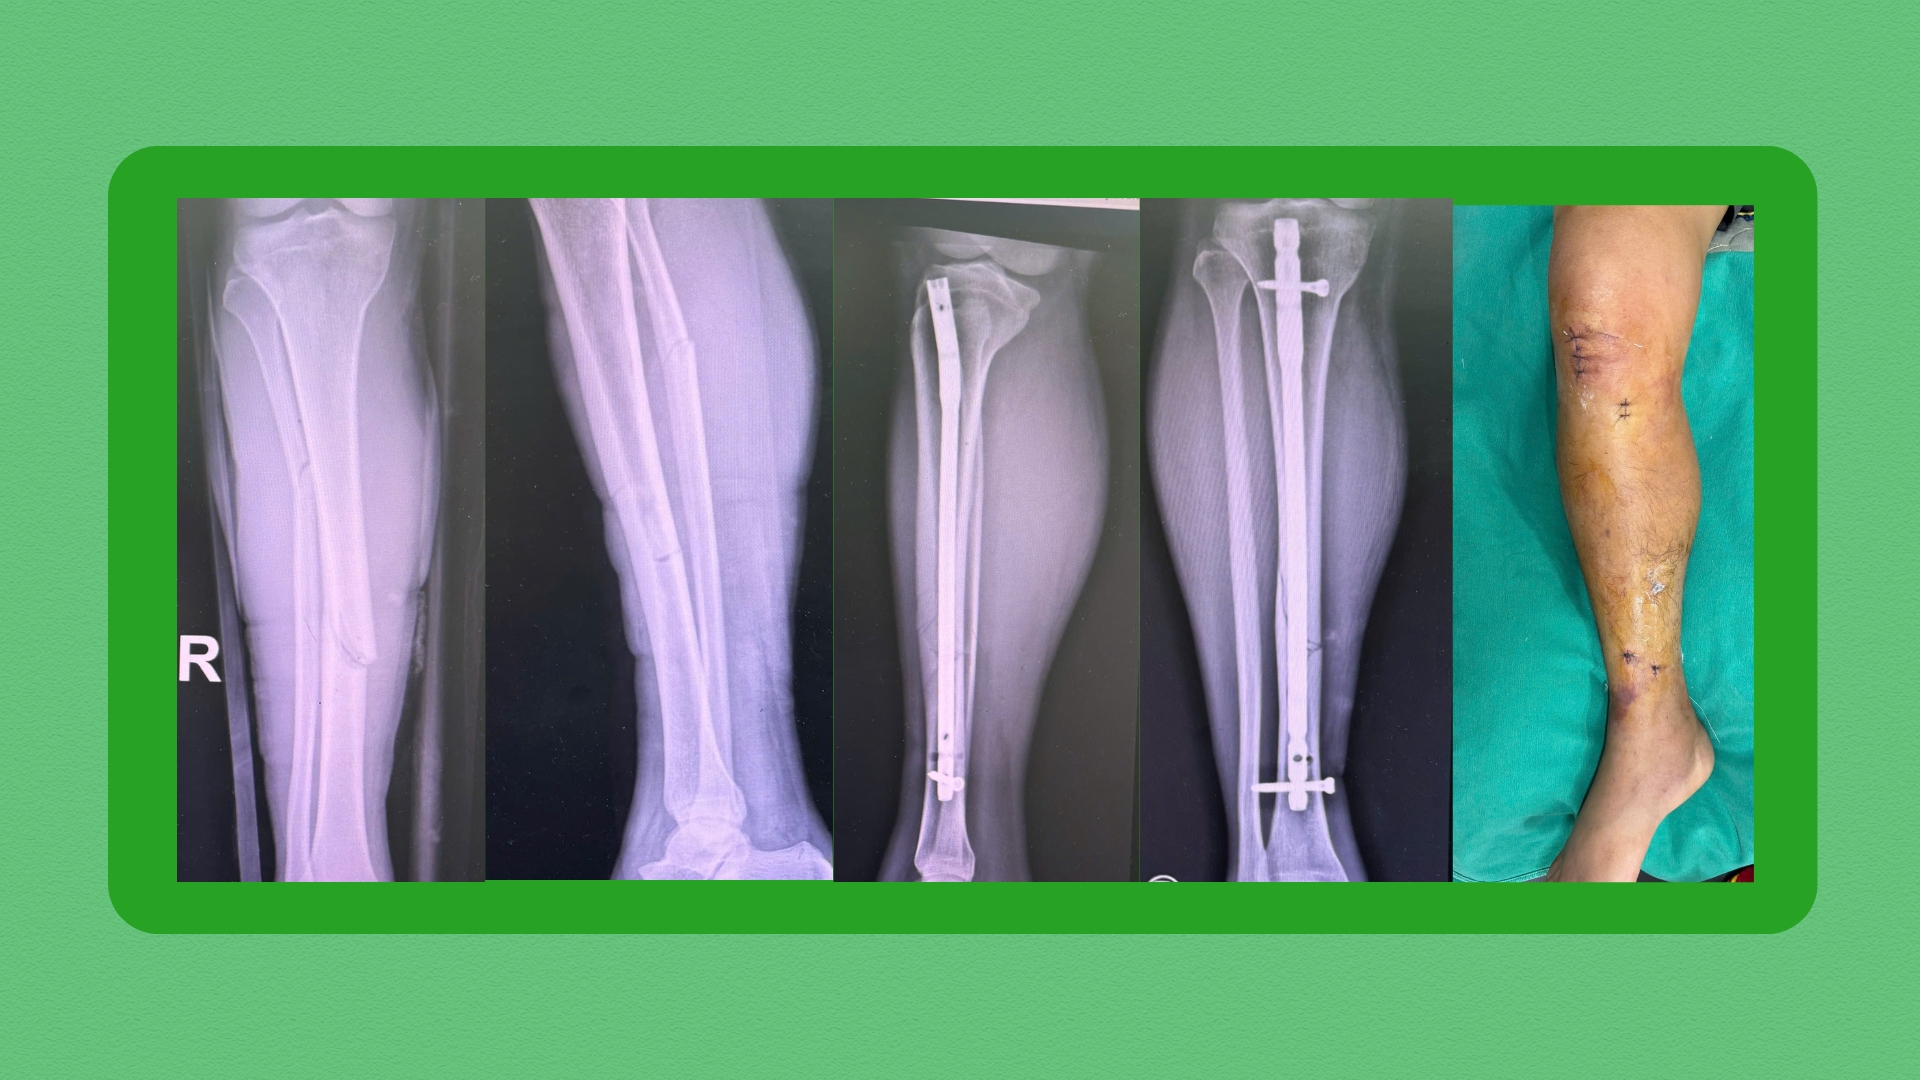

Một số hình ảnh trước và sau phẫu thuật của bệnh nhân được sử dụng kỹ thuật MIPO trong phẫu thuật kết hợp xương

Hình ảnh phim chụp của bệnh nhân T. trước và sau phẫu thuậtQua thăm khám lâm sàng và xét nghiệm cận lâm sàng, bệnh nhân được chẩn đoán xác định gãy phức tạp đầu trên xương chày trái. Sau hội chẩn, các bác sĩ quyết định thực hiện phương pháp kết hợp xương nẹp vít bằng MIPO, nắn chỉnh kín dưới màn tăng sáng C-arm.

Chỉ sau một ngày phẫu thuật, bệnh nhân đau nhẹ, ít sưng nề, đã được tiến hành tập phục hồi chức năng các bài tập chủ động như gấp duỗi cổ chân, gối và khớp háng. Chia sẻ sau phẫu thuật, bệnh nhân cảm thấy rất hài lòng và tin tưởng phương pháp điều trị.